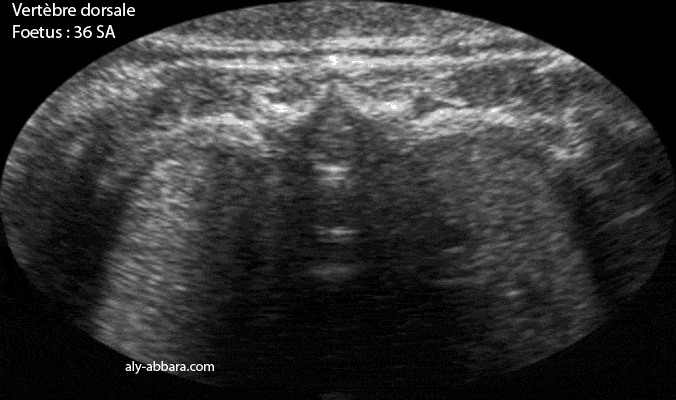

Vertèbre thoracique - grossesse de 36 semaines d'aménorrhée

Image échographique montrant les structures anatomiques individualisables d'une vertèbre thoracique chez un fœtus de 36 SA

A comparer à une vertèbre lombaire